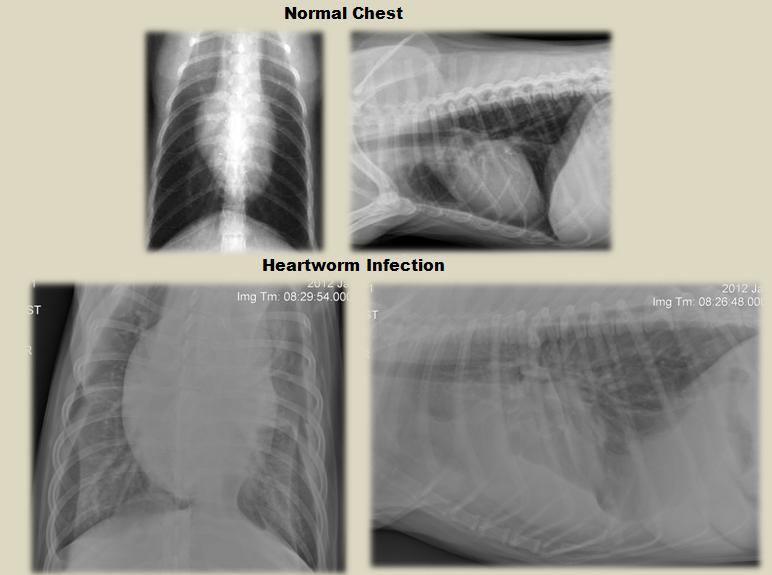

Diagnosing and Treating Heartworm Infection in Dogs Dog Worms Heart There are four classes, or. Dogs that have heavy worm burdens, have been infected for a long time, or are very active often show obvious symptoms of heartworm disease. Most dogs are highly susceptible to heartworm infection, and the majority of infective larvae develop into adult worms. It's been found in all 50 u.s. Heartworm in dogs is a potentially. Dog Worms Heart.